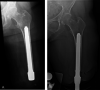

Background: Septic loosening and stem breakage due to metal fatigue is a rare but well-known cause of orthopaedic implant failure. This may also affect the components of the osseointegrated implant system for individuals with transfemoral amputation who subsequently undergo revision. Identifying risk factors is important to minimize the frequency of revision surgery after implant breakage.

Results: Thirty-four percent (20 of 58) of patients had revision surgery. In 12% (7 of 58) of patients, the reason for revision was due to intramedullary stem failures (six breakages, one septic loosening), and in 22% (13 of 58) of patients it was due to dual-cone adaptor failure (10 weak-point breakages and four distal taper breakages; one patient broke both the weak-point and the dual-cone adapter). Smaller median stem diameter (failure: 15 mm [interquartile range 1.3], nonfailure: 17 mm [IQR 2.0], difference of medians 2 mm; p < 0.01) and higher median number of infectious events (failure: 6 [IQR 11], nonfailure: 1 [IQR 3.0], difference of medians -5; p < 0.01) were associated with revision intramedullary stem surgery. No risk factors could be identified for broken dual-cone adapters.

Conclusion: Possible risk factors for system failure of this osteointegration implant include small stem diameter and high number of infectious events. We did not find factors associated with dual-cone adapter weak-point failure and distal taper failure, most likely because of the small sample size. When treating a person with a lower-limb amputation with a CoCrMb osseointegrated implant, we recommend avoiding a small stem diameter. Further research with longer follow-up is needed to study the success of revised patients.